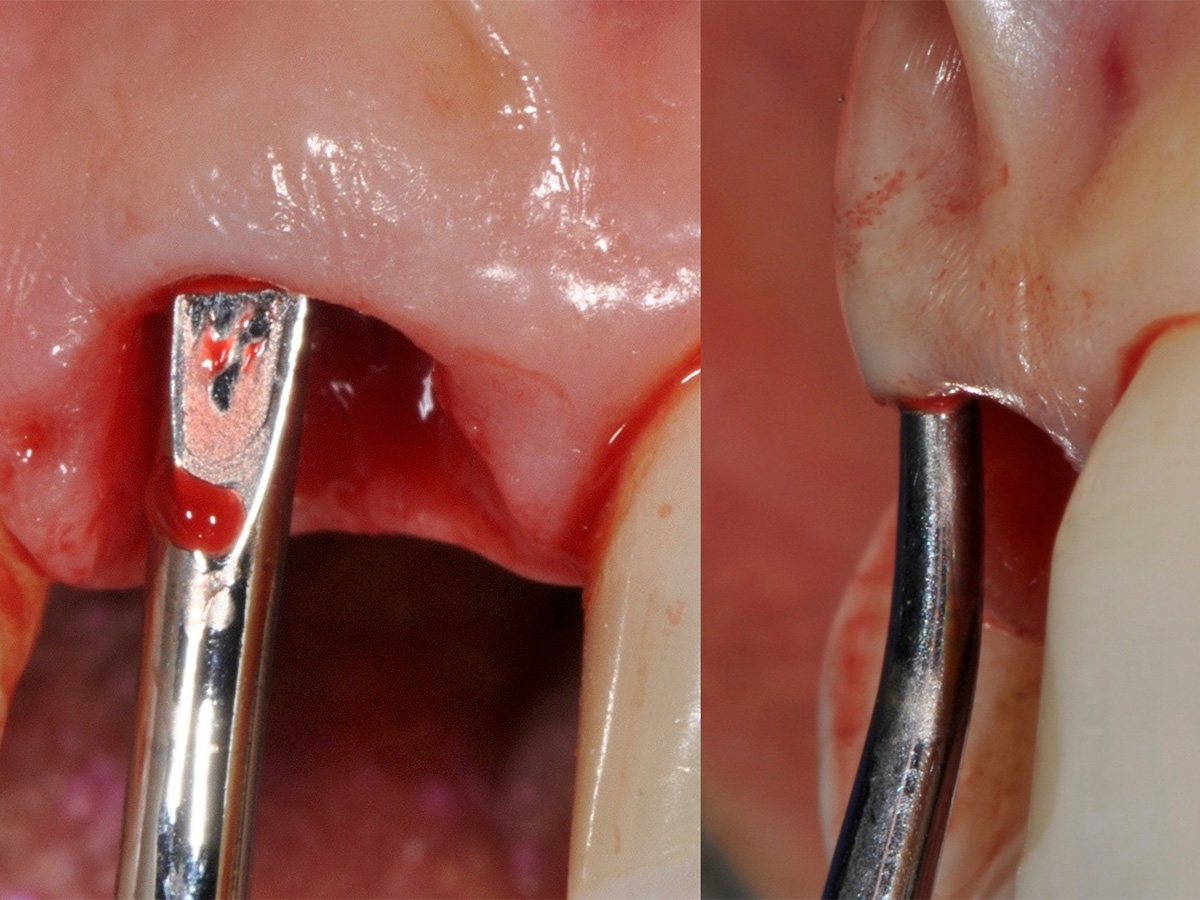

Die dreidimensionale Aufnahme verdeutlicht den nach der Extraktion des Zahns zu erwartenden Defekt. Trotz schonender Extraktion, ohne aufzuklappen, konnte das Fehlen der knöchernen bukkalen Lamelle ertastet werden. Es folgten die Präparation und die Erweiterung des Implantatbetts. Die palatinale Positionierung von Implantaten liefert in der Regel gute Ergebnisse hinsichtlich der Implantaterfolgsrate, der Stabilität des periimplantären Gewebes, des Knochenverlusts und der Patientenzufriedenheit. Das Implantat ließ sich in der idealen Position primärstabil inserieren. Zur Regeneration der knöchernen Lamelle wurde die Bone-Lamina-Technik verwendet: Es wurde ein Mukoperiostlappen mit dem Tunnelinstrument präpariert, um die porcine kortikale Knochenmatrix (Osteo- Biol Soft Cortical Lamina, Tecnoss) einbringen zu können. Die Präparation wurde minimalinvasiv und ohne Inzision durchgeführt. Die Distanz zwischen dem palatinal inserierten Implantat und der bukkal eingebrachten Bone-Lamina füllten wir mit resorbierbarem knochenregenerativem Material, der deproteinierten bovinen Knochenmatrix OsteoBiol mp3 (Tecnoss), auf. Vor dem Eingriff wurde eine Funktionsanalyse durchgeführt und Meistermodelle wurden angefertigt. Da das Implantat sehr primärstabil eingebracht werden konnte, wurde direkt nach der Operation ein Abformpfosten gesetzt und mit einem Index versehen. Dadurch kann ohne eine Abformung die exakte Implantatposition dem Zahntechniker übermittelt werden. Postoperativ wurde der Patient instruiert, dreimal täglich mit 0,2 % Chlorhexidindigluconat bis zur Nahtentfernung zu spülen. Zusätzlich wurden für drei Tage Ibuprofen 600 mg, Amoxicillin und Clavulansäure verschrieben.

Es wurde ein Mukoperiostlappen mit dem Tunnelinstrument präpariert...

Abbildung 5

... um die porcine, kortikale Knochenmatrix (OsteoBiol Soft Cortical Lamina, Tecnoss) einbringen zu können.